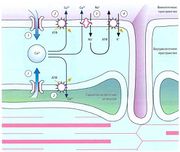

| 03:23, 20 июля 2016 | Mishci sport74.jpg (файл) |  |

39 КБ | Anes | Входной и выходной потоки ионов Са2+ в электромеханическом сопряжении при сокращении сердца | 1 |